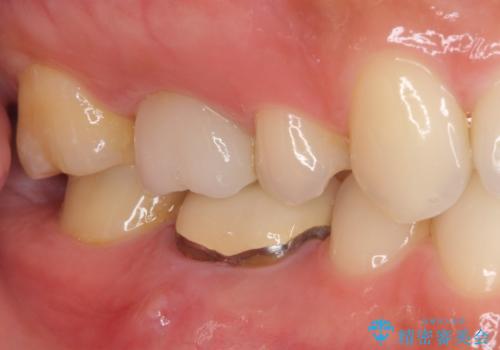

- 歯肉の退縮に伴い、金属を用いたクラウンの縁が見えてしまうことを気にして来院された患者様です。

歯肉には膿の出口が見られ、レントゲン写真からは歯根周辺に病変が認められたため、まずは根管治療を行い、その後フルジルコニアクラウンにて補綴することとしました。